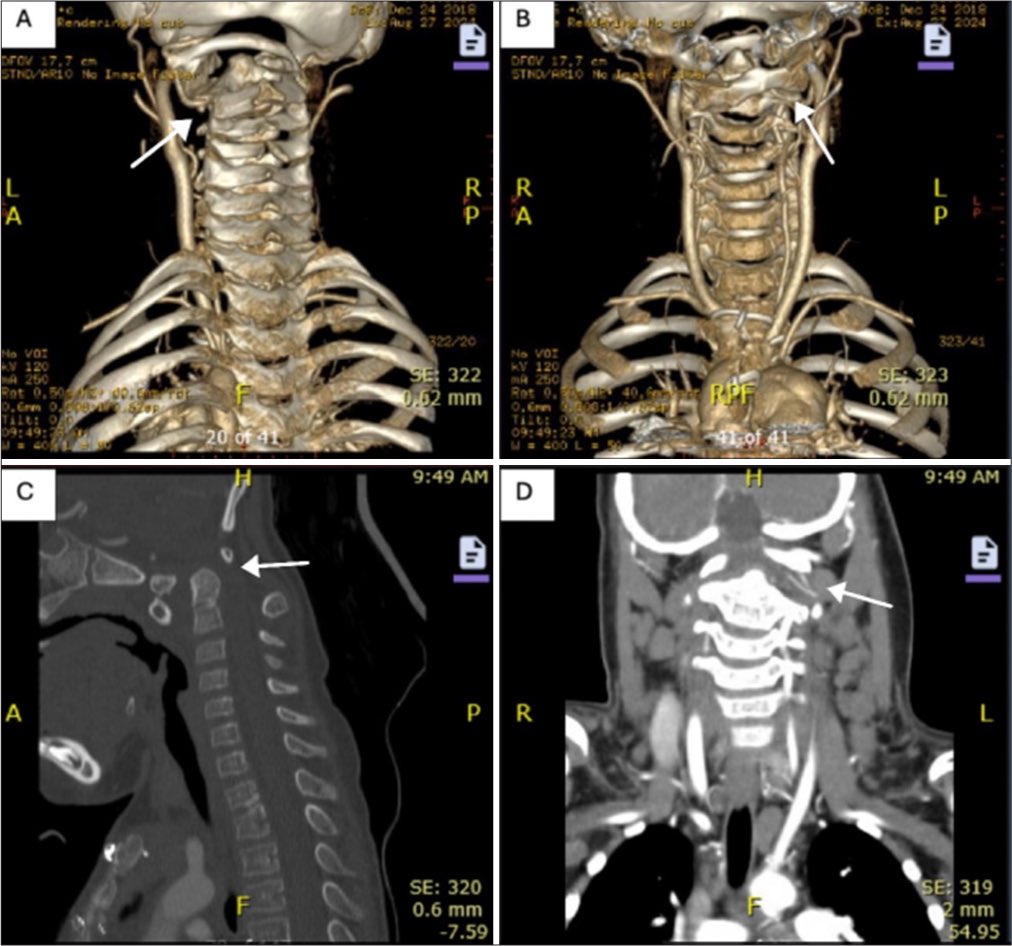

جدة.. "عملية الـ 12 ساعة" تُغلق تمدداً شريانياً عملاقاً في رأس مريضة sabq.org/jzSvgL @sabqorg